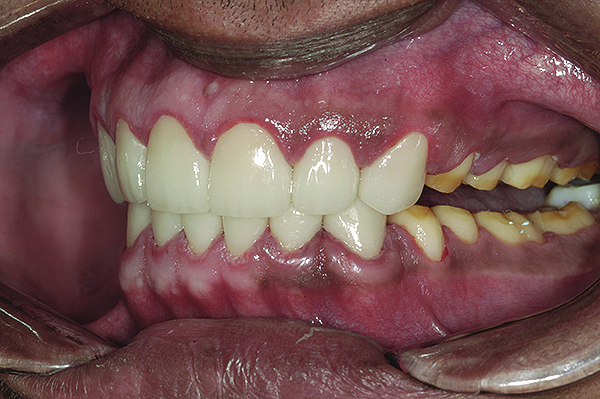

Figure 16. Anterior final restorations bonded.

Figure 16

The final restorations depicted restoration of form, function, and beauty, with good harmony of restoration and the periodontium (Figure 19 through Figure 25). MIP was in harmony with CR, and right and left lateral excursion discluded all posteriors with anterior group function. The postoperative orthopantomogram (OPG) (Figure 26) shows the treatment done while maintaining the vitality of anterior teeth.